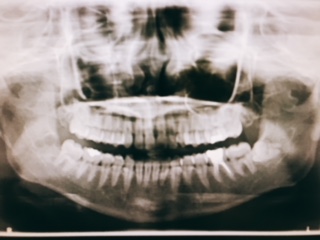

先日、私は右下の親知らずを抜歯しました!

向かって左下に薄っすらと写っている歯です。

親知らずの一本手前の歯に違和感があり・・・・

もしかして虫歯❓と不安になり先生に相談したところ

親知らずの影響という事がわかりました。

ひとまず、虫歯ではなかった事に安心✨

そして親知らずは抜歯したほうが良いとの事でした。